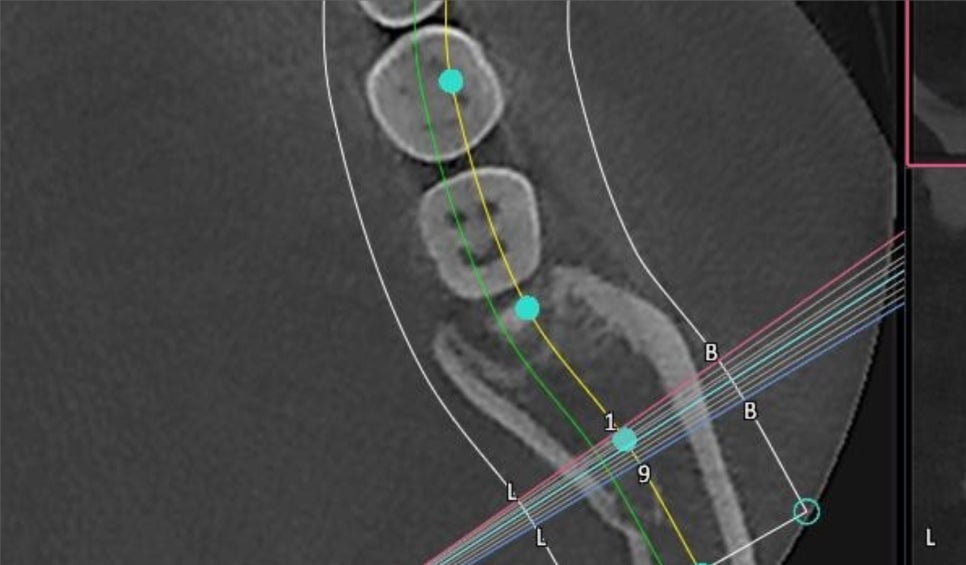

사랑니 뿌리 끝과

중요한 하치조신경관이 가까워

CBCT를 찍어 분석했는데

다행히 문제가 없어 보여서

누운 사랑니를 뽑을 때는 이렇게

앞쪽 치아 머리를 잘라내고

뽑아야 하는 경우가 많습니다.

치아를 뽑아 건져올릴 때

빙산처럼 아래 잠긴 부분이

앞에 치아에 걸려서 못 빠져나오거든요.